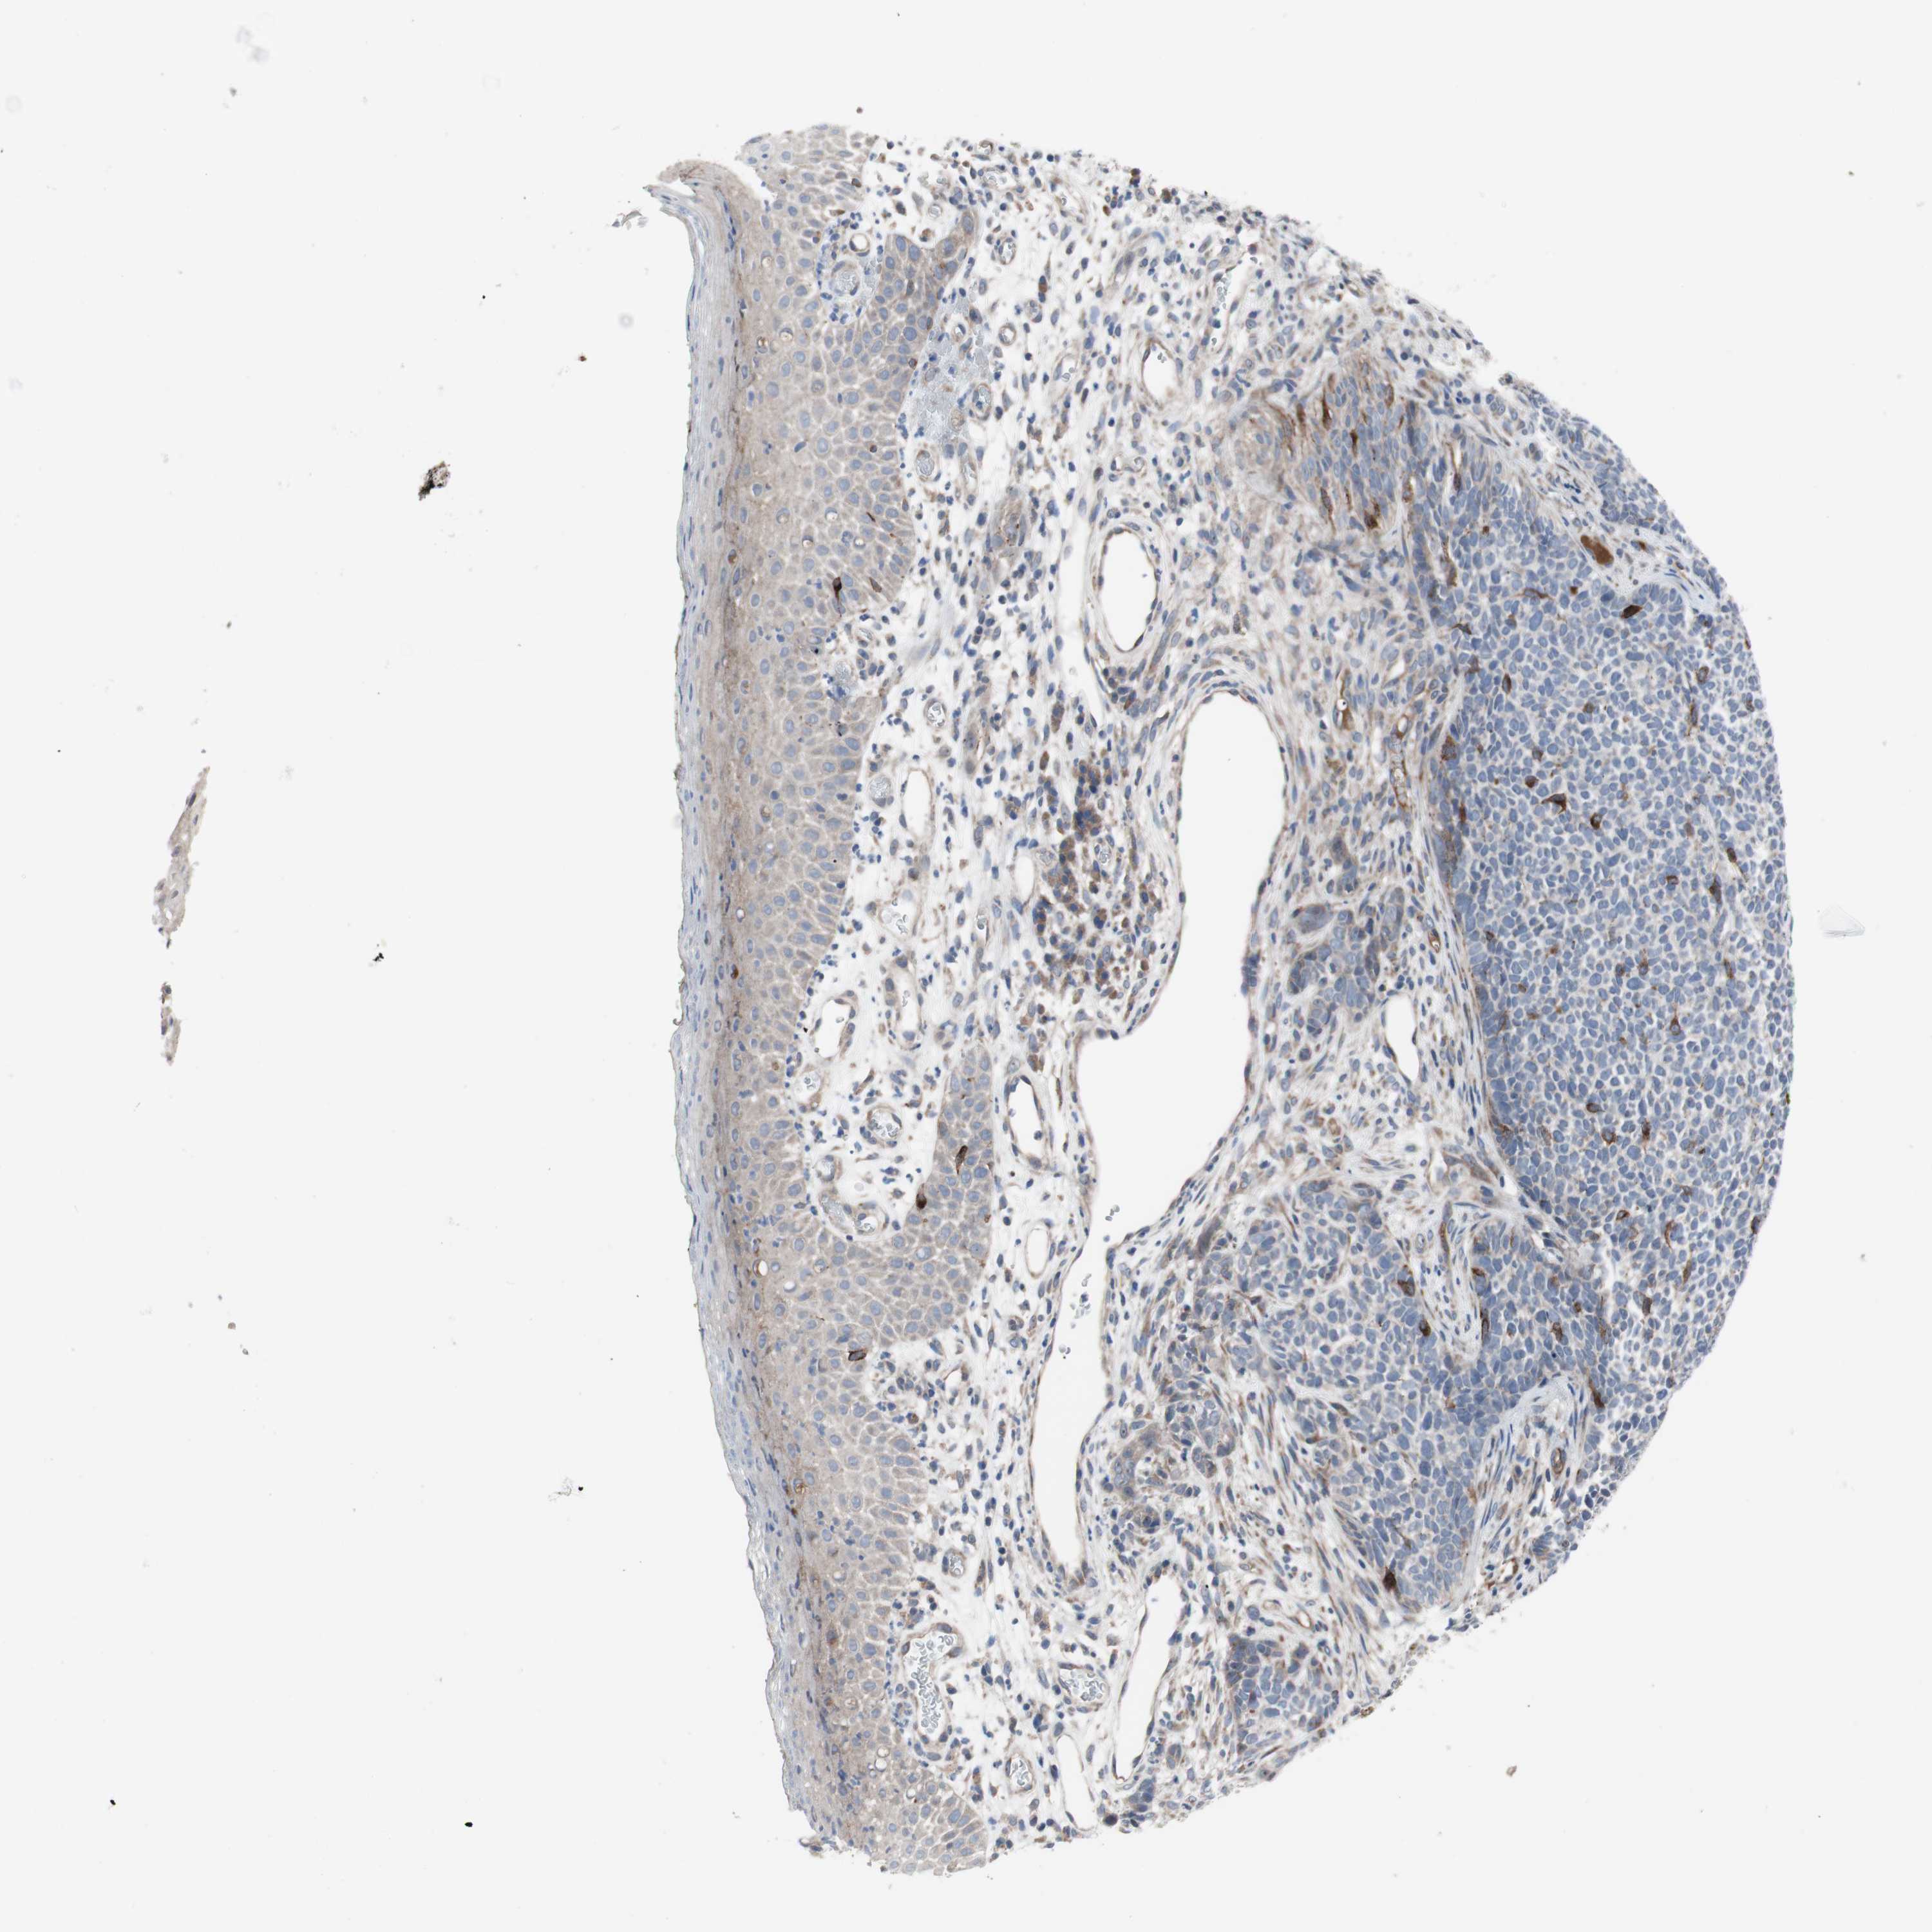

SKIN CANCER - Protein expressioni

A mouse-over function shows sample information and annotation data. Click on an image to view it in a full screen mode. Samples can be filtered based on level of antibody staining by selecting one or several of the following categories: high, medium, low and not detected. The assay and annotation is described here.

Antibody staining in the annotated cell types in the current human tissue is reported as not detected, low, medium, or high, based on conventional immunohistochemistry profiling in selected tissues. This score is based on the combination of the staining intensity and fraction of stained cells.

Each image is clickable and will lead to virtual microscopy that enables deeper exploration of all samples and also displays staining intensity scores, fraction scores and subcellular localization as well as patient and tissue information for each sample.

Antibody HPA006874

Antibody HPA007208

Staining

High

Medium

Low

Not detected

Intensity

Strong

Moderate

Weak

Negative

Quantity

>75%

75%-25%

<25%

None

Location

Nuclear

Cytoplasmic/membranous

Cytoplasmic/membranous,nuclear

Squamous cell carcinoma, NOS

Basal cell carcinoma